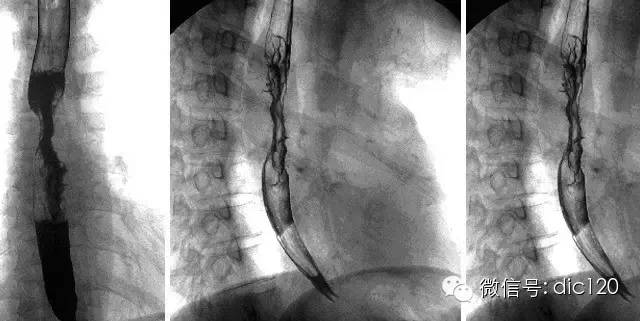

【病史臨床】男,63歲,胸痛,進行性吞咽困難伴消瘦20天。

【影像表現(xiàn)】 CT:表現(xiàn)現(xiàn)為食管壁明顯增厚,管腔狹窄;食管與周圍結(jié)構(gòu)分界不清食管吞鋇:食管中段充盈缺損,管腔不規(guī)則狹窄,管壁僵硬,粘膜糾集破壞,與正常食管壁分界清晰。

【診斷】 病理診斷:食管(中下段)高-中分化鱗狀細胞癌,侵及食管壁全層。(圖1.2)